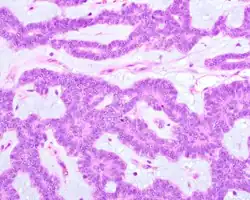

Canalicular adenoma growths are usually small at the time they are noticed, with an average size of about 1.6 cm.[1] Their histologic appearance is very distinct, with a channel-like pattern between cords and ribbons; the pattern has been described as resembling a "string of pearls."

The growths often contain are often small bight squamous balls, or morules. They also typically contain a well-developed supporting tissue - a fibrous stroma - which is rich in hyaluronic acid and chondroitin sulphate.[1] In a few cases, the growths may contain small calcium deposits or microliths. Although it is seldom necessary, a pathologist can confirm the existence of canalicular adenoma through immunohistochemistry studies, with the cells reacting with pancytokeratin, S100 protein and SOX10, with a delicate GFAP reaction around the periphery.[5][1][6][7] Although it is a benign tumor, a positive diagnosis of canalicular adenoma may be necessary to exclude the existence of other medical conditions such as a basal cell adenoma, pleomorphic adenoma, adenoid cystic carcinoma, and polymorphous adenocarcinoma.